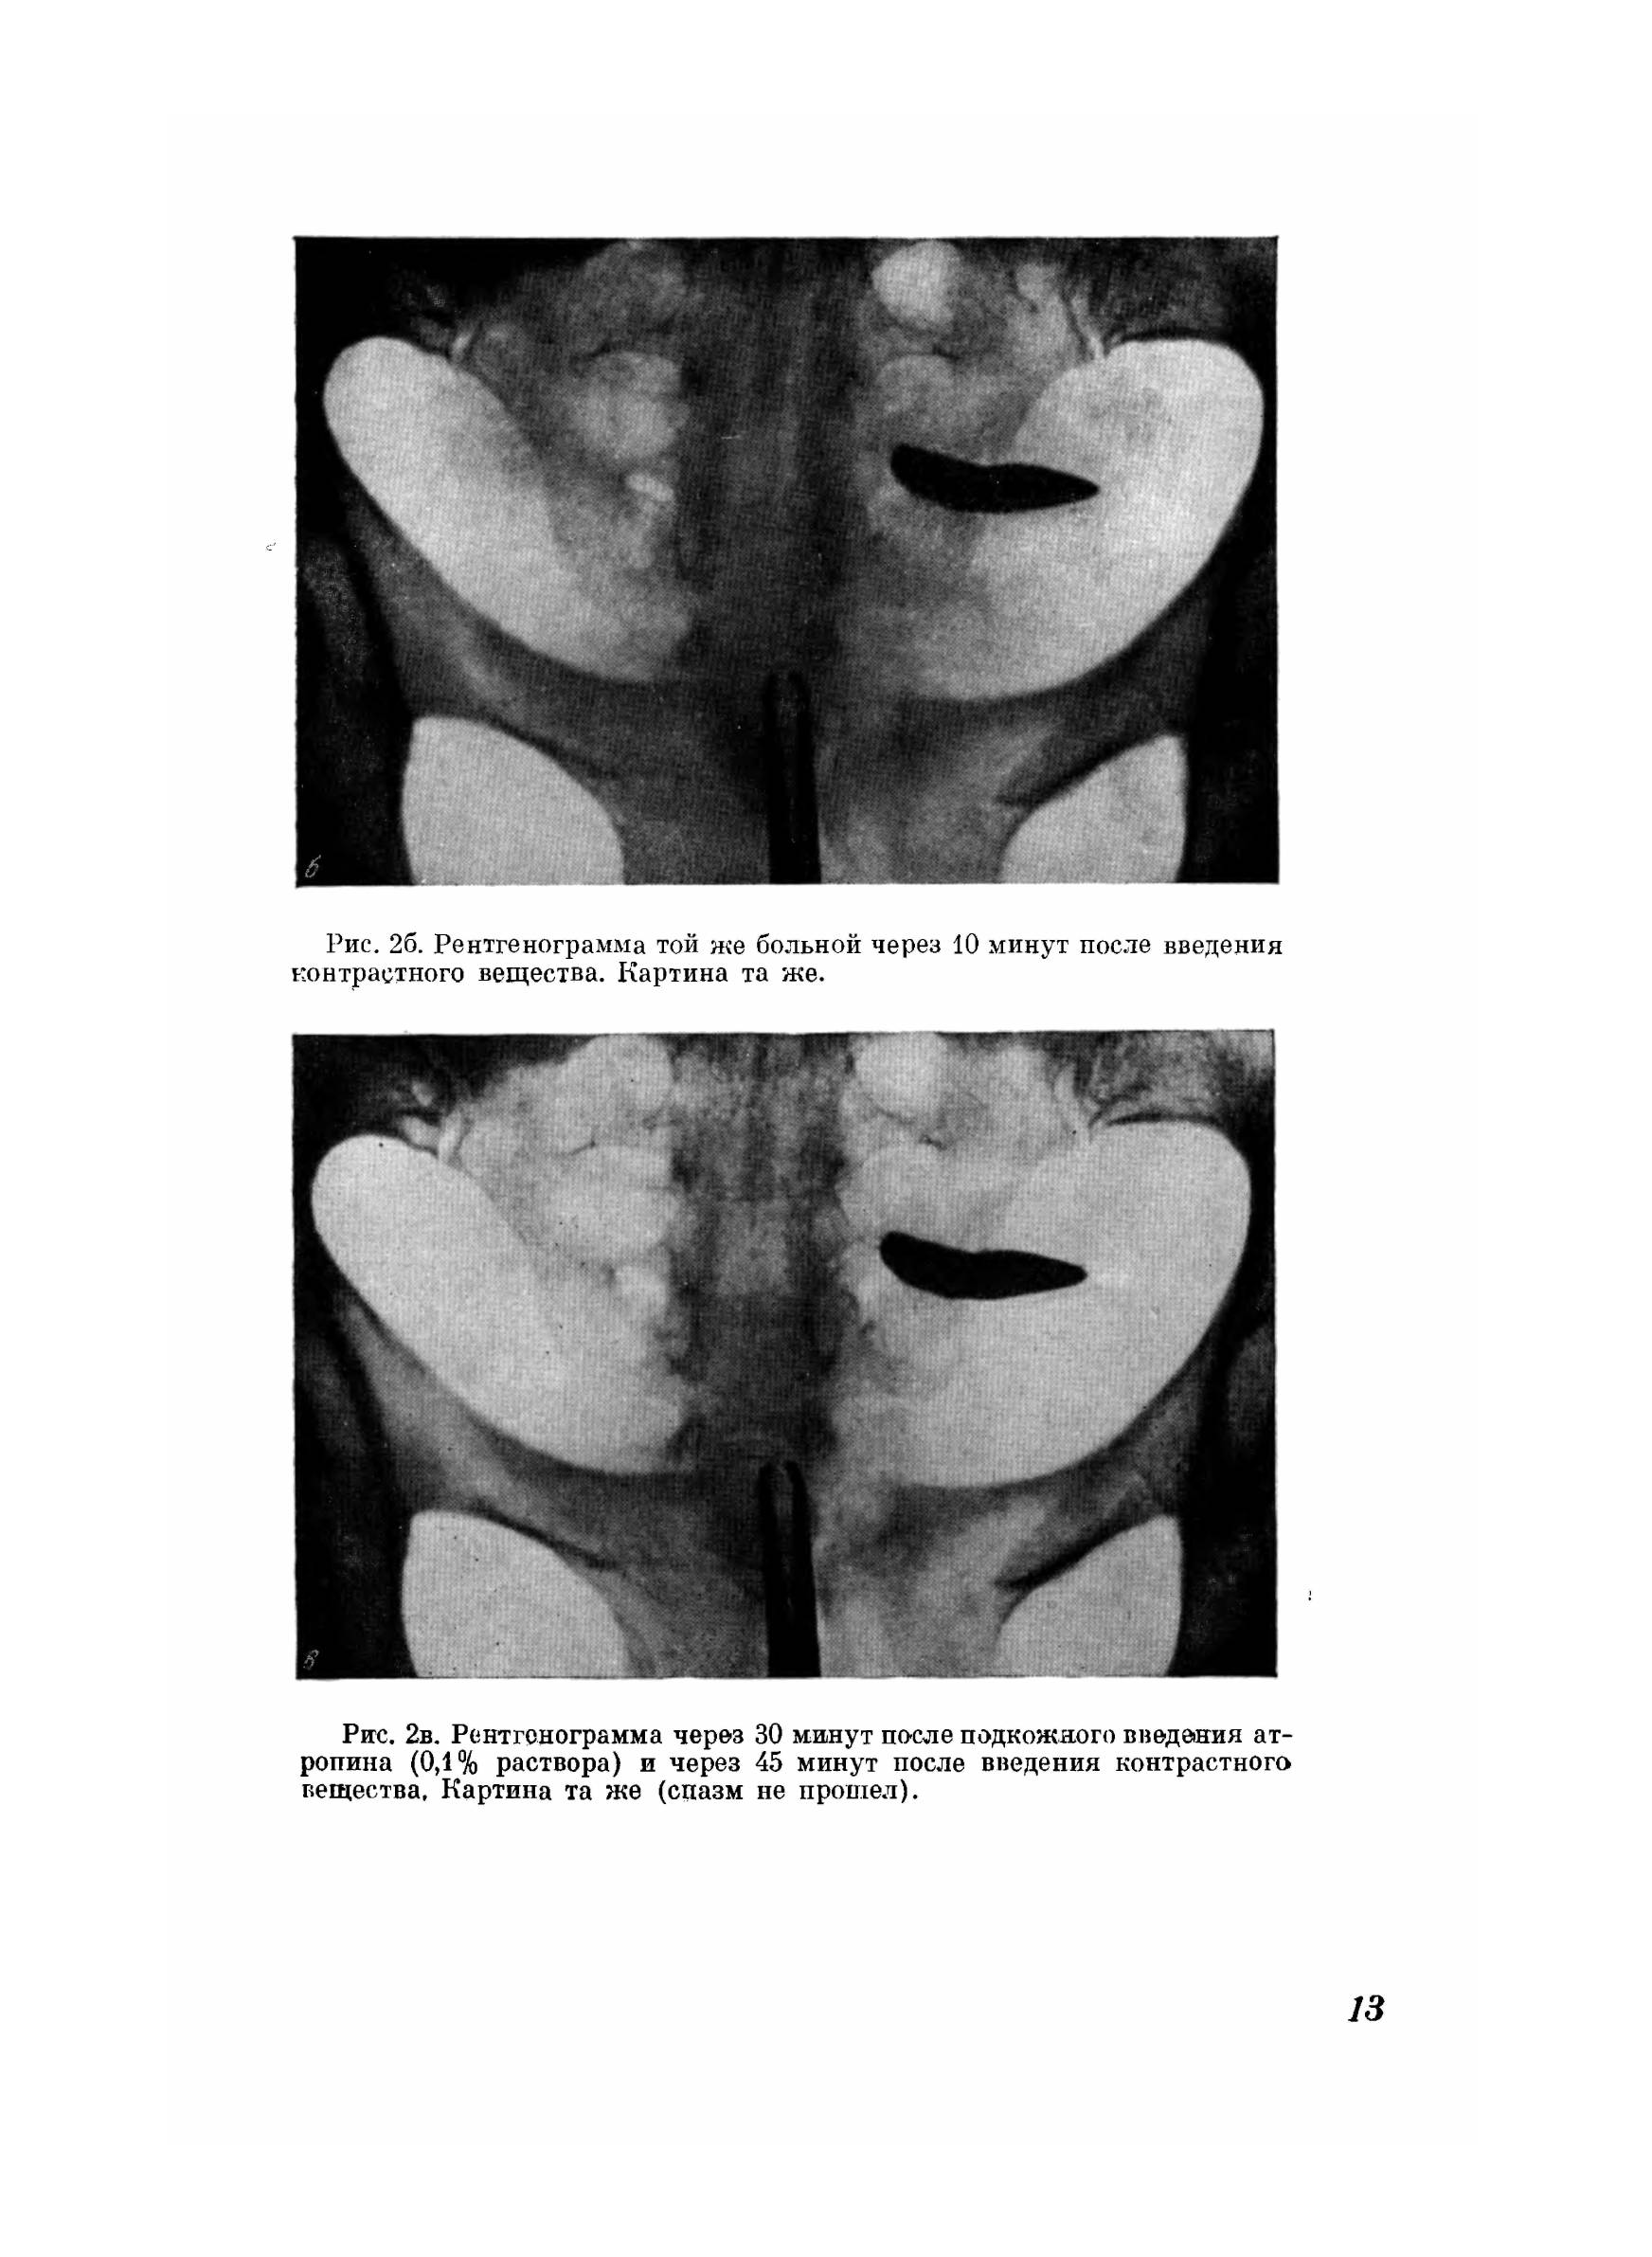

Рентгенологическая диагностика патологических изменений женских подовых органов с помощью контрастной гистеросальпингографии все шире и шире находит практическое применение, она помогает поставить правильный диагноз и применить целесообразный метод лечения. Многие врачи-гинекологи вследствие неумения читать рентгенограммы предоставляют их на интерпретацию рентгенологам общего профиля, которые дают заключение без достаточных знаний гинекологии, не учитывая особенности условий и техники проведения гистеросальпингографии. Гистеросальпингографии является объективным и документальным методом в оценке проходимости или непроходимости труб. В этом заключается одно из преимуществ его перед продуванием последних. Гистеросальпингография дает четкие контуры слизистой матки и труб и дефекты наполнения их полостей, на основании которых можно установить тот или иной диагноз (туберкулезный эндометрит, эндометриоз, полипы, миомы и т. д.). Желание помочь практическому врачу в проведении гистеросальпингографии и дать возможность разобраться в многообразных рентгенологических картинах привело нас к мысли поделиться своим опытом и выпустить альбом, в котором помещено около 150 рентгенограмм, размещенных по разделам соответственно тематики. Считаем, что подготовка кадров акушеров-гинекологов, владеющих не только правильной техникой гистеросальпингографии, но и умением хорошо разбираться в каждой рентгенограмме, обеспечит наиболее правильную диагностику и своевременное применение рациональной терапии.